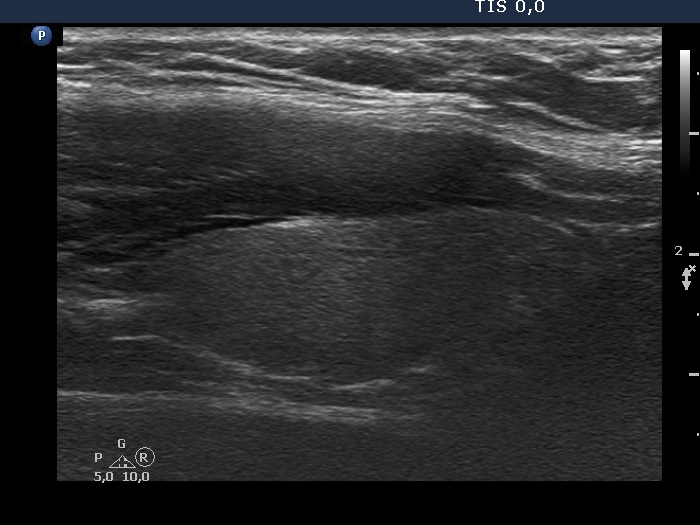

The composition of the nodule - case 51 (ultrasonographic picture 5)

Left lobe, longitudinal scan.